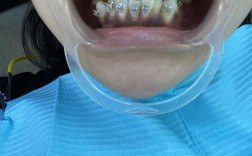

金属矫正器效果如何?矫正过程疼不疼?

牙齿矫正金属矫正器,作为临床应用最广泛、历史最悠久的正畸装置,通过机械性外力引导牙齿移动至理想位置,是解决各类错颌畸形的重要手段,其核心结构由托槽、弓丝、结扎丝或橡皮圈组成,其中托槽通常由不锈钢或钛合金制成,通过专用粘接剂固定于牙齿唇颊面,...